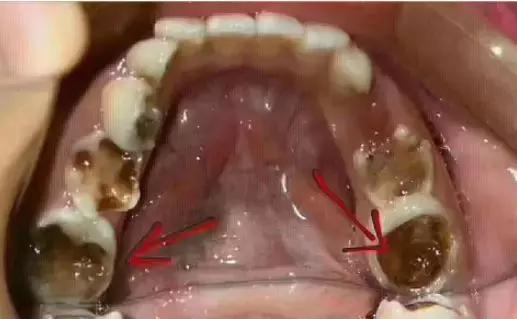

8颗乳牙,4颗恒牙全蛀空

4月21日上午,一位患者妈妈利用周末休息,带着自己十岁的儿子匆匆忙忙地赶到口腔医院来补牙,医院口腔牙医给小患者在牙床上仔细检查后,惊讶的发现这个小朋友口腔情况非常糟糕,孩子的牙全被蛀空了,只剩下残根。

医生检查发现,孩子所有乳磨牙、六龄牙和新生前磨牙都已经蛀空,无奈之下,孩子妈妈只能听从医生建议,把孩子的牙根全部拔除,再安装上活动假牙,来维持正常的咀嚼功能。